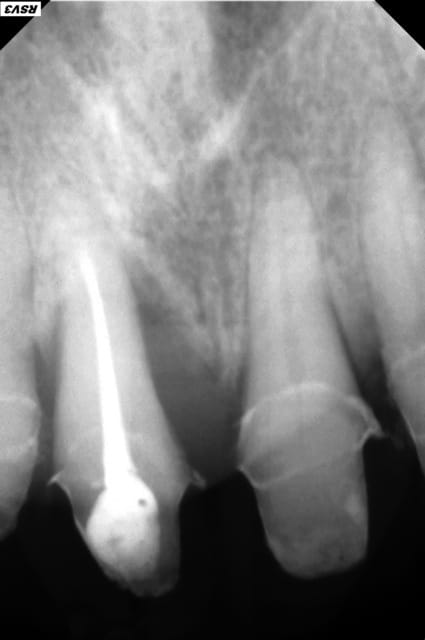

j'ai été un peu présomptueux sur mes capacités à conserver 11,

je doit me résoudre à l'extraire,

La perte paro importante sur 11, l'égression des 11 et 21 avec diastème et l'usure importante montrent un manque de calage postérieur existant depuis un bon moment (présence certaine d'une PAP maxillaire, non adaptée, non rebasée). Il n'y a pas de raison que tout cela s'arrange juste en refaisant les incisives sup.

Pour la ligne du sourire, difficile de dire si cela aura un impact (pas de photo de sourire disponible), mais vu la perte osseuse visible sur la rétro, il y a fort à parier que tu vas te retrouver avec une belle fonte de la corticale vestibulaire quelques mois après extraction: comblement bio-oss possible+travail de l'esthétique de l'émergence du pontique.

Cependant un traitement implantaire (11 et surement 21 aussi) donnerait un résultat esthétique plus durable, bien qu'évidement ici l'économie tissulaire et le budget sont sacrifiés sur l'autel de l'esthétique, et j'en vois déjà ici crier au scandale ;-).

Mais honnêtement je pense que d'un point de vue esthétique ce cas tient d'un traitement implantaire sur 11 et 21 (avec comblement osseux pour 11) et évidement toujours après réhabilitation du calage postérieur.